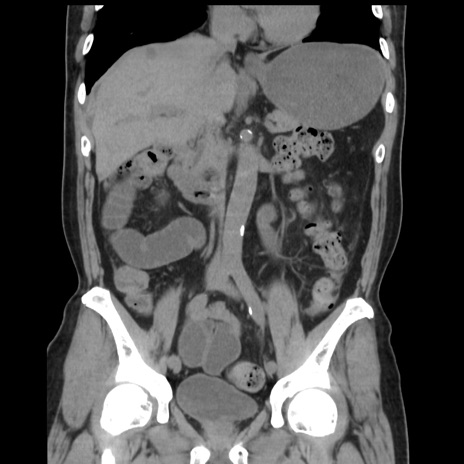

症例16(冠状断像)

【現病歴】 約1ヶ月前より間欠的に腹痛と嘔吐あり、当院消化器内科を受診したところCTで多発する肝臓のLDAを指摘され、精査中であった。以降は消化器症状は安定していたが、2日前より嘔気と腹痛があり、同日より排便・排ガスが消失した。改善認めず、 本日、救急外来を受診した。